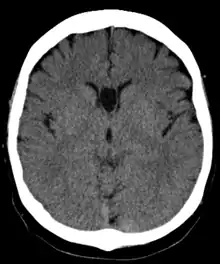

The cave of septum pellucidum (CSP), cavum septi pellucidi, or cavity of septum pellucidum is a slit-like space in the septum pellucidum that is present in fetuses but usually fuses during infancy. The septum pellucidum is a thin, laminated translucent vertical membrane in the midline of the brain separating the anterior horns of the right and left ventricles. It lies posterior to the corpus callosum. Persistence of the cave of septum pellucidum after infancy has been loosely associated with neural maldevelopment and several mental disorders that correlate with decreased brain tissue.[1][2][3][4][5]

The cave of septum pellucidum is bounded anteriorly by the genu of the corpus callosum, superiorly by the body of the corpus callosum, posteriorly by the anterior limb and pillars of the fornix, inferiorly by the anterior commissure and the rostrum of the corpus callosum, and laterally by the leaflets of the septum pellucidum.[6]

In prenatal development of the fetus, the laminae of the septum pellucidum separate to form a small cavity – the cave of septum pellucidum. This is an important normal structure to identify in the sonographic assessment of the fetal brain. In post-natal life, the laminae of the septum pellucidum usually fuse, which obliterates the cavum. The cavity contains cerebrospinal fluid (CSF) that filters from the ventricles through the septal laminae.[7]

There are individual differences in the degree of CSP; whereas some have complete closure of the cavum, others present with a small degree (4–6 mm wide, in the coronal plane) of incomplete closure.[4] The most common type of CSP is noncommunicating; that is, it does not connect to the brain's ventricular system. Because of this lack of communication, the previous use of the term "fifth ventricle" is no longer used, and the fifth ventricle is the name often used for the terminal ventricle.

CSP is present in 100% of fetuses, but over 85% of them fuse by 3–6 months after birth.[8][9]